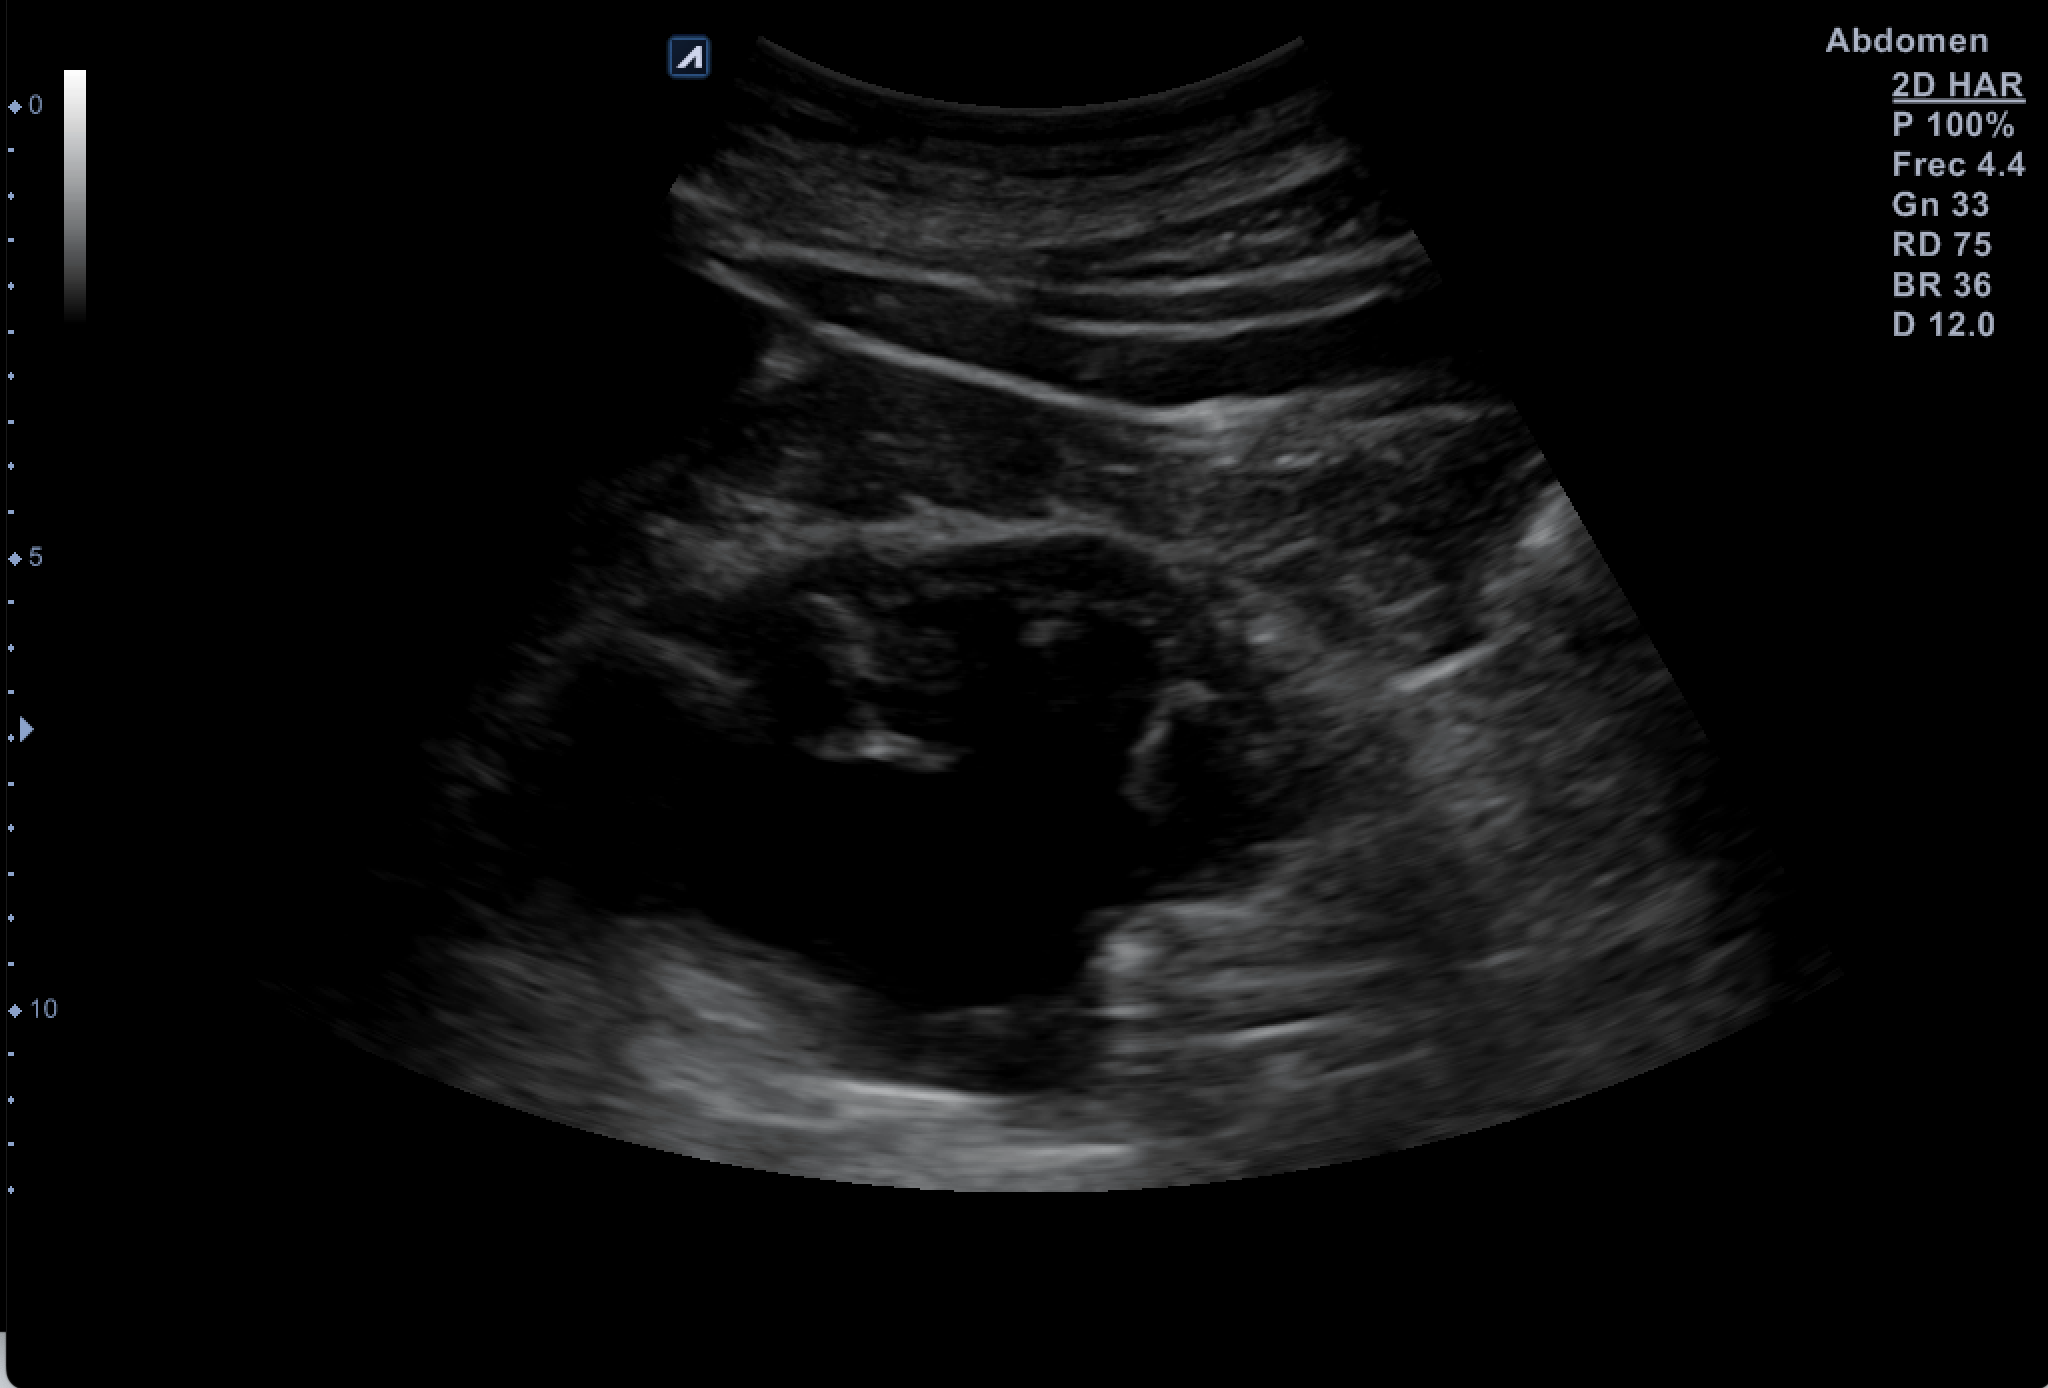

Hallazgos ecográficos

Tras valoración vesicoprostática con vejiga normal, jet vesicales visibles con próstata de 45 cc y residuo postmiccional mínimo. Riñón derecho como normal de tamaño y morfología sin dilataciones pielocaliciales (11 cm de tamaño). El Riñón Izquierdo (RI: 9 cm) presentaba una hidronefrosis grado IV y atrofia cortical con pelvis renal distendida, no consiguiendo detectar la causa obstructiva y considerando la posibilidad de una estenosis de la unión pieloureteral y como segunda opción una litiasis  ureteral pese a la normalidad de los jets vesicales.